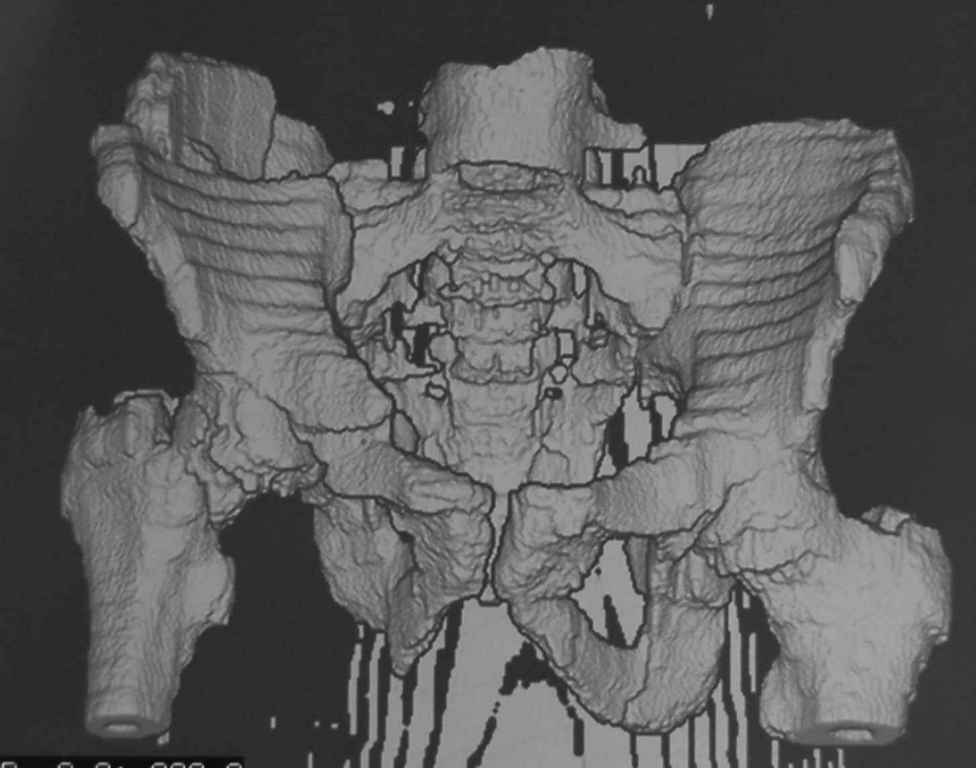

Принципиально важно видеть все срезы КТ через вертлугу, так как тактика лечения будет в первую очередь обусловлена характером перелома ветрлужной впадины, во вторую - вертикальным смещением таза ( где варианты - от банального скелетного вытяжения до ВЧКО или накостного остеосинтеза - в основном зависит от пресловутой "позиции кафедры")

Уважаемый Алексей, на представленных Вами снимках имеется вертикально-нестабильное повреждение тазового кольца без повреждения вертлужной впадины. Учитывая это, а так же растущий возраст ребенка я бы выбрал аппарат внешней фиксации в виде кольцевой опоры, т.к. не смотря на оскольчатый перелом крыла в переднем отделе можно ввести минимум 2 стержня + 1-2 надвертлужно. Этого будет достаточно чтобы "зацепится", выполнить репозицию и дальнейшую фиксацию. Перелом шейки по моему лучше прооперировать 3 канюлированными винтами по АО.

1 аппаратом сложно управлять при оскольчатом переломе крыла